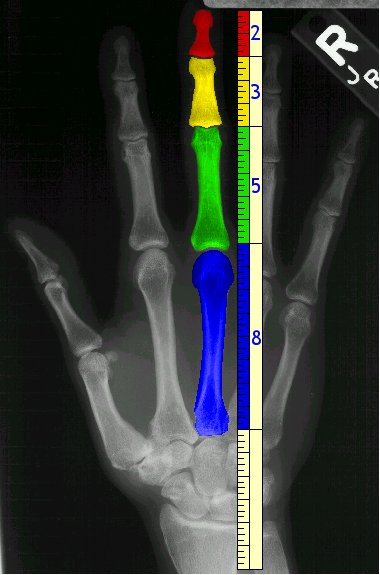

About a quarter of the motor cortex is devoted to controlling the hands. Left or right handedness is controlled by the opposite side of the brain, and is indicative of individual brain functioning. Michelangelo painted with both hands. The lengths of the bones in our fingers approximate a Fibonacci sequence. Fingernails grow about as much as the continents move every year. Fingerprints are permanent and unique to each person, making them dependable for personal identification. Palmistry is the (less dependable) practice of reading someone's life - past, present and future - from their hands. Chirophobia is the fear of hands. Polydactyly is the presence of extra fingers or toes. There are 174 words beginning with, 324 words containing, and 22 words ending with "hand." Also check out these "50 handy expressions about hands."